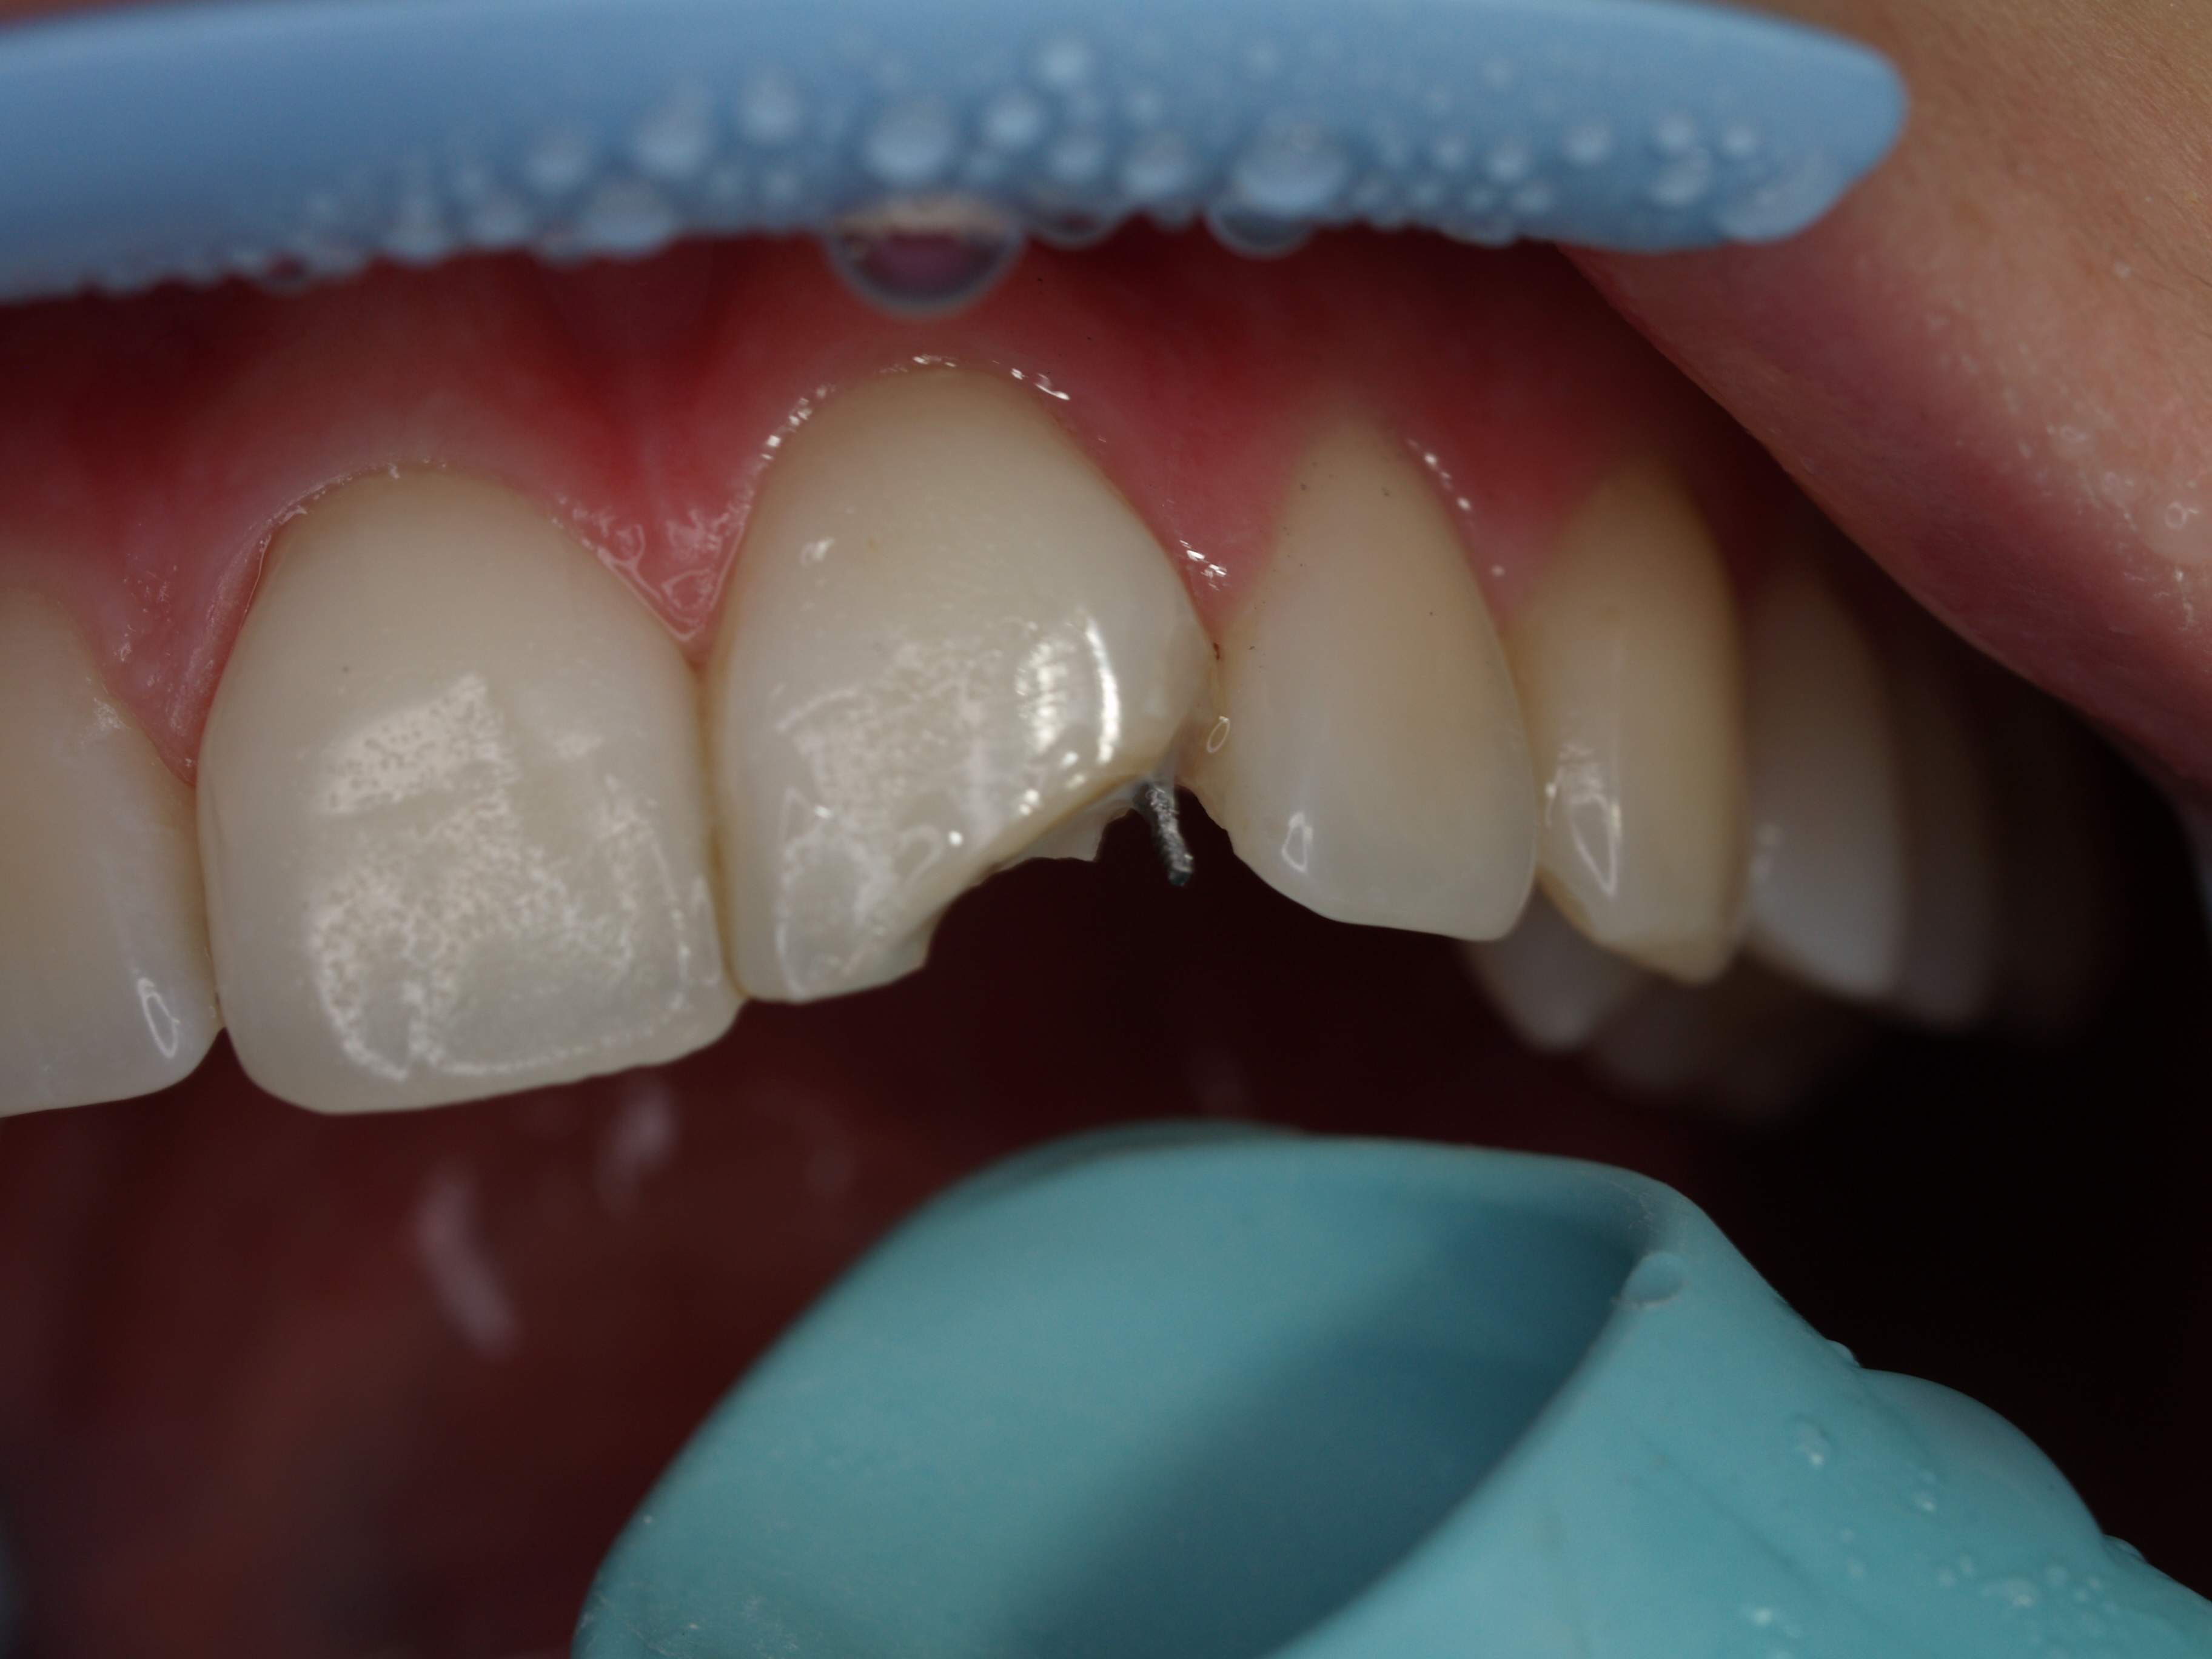

Nieestetyczne wypełnienie w zębie 21 skłoniło pacjentkę do jego wymiany. Podczas badania stwierdzono obecność ćwieka okołomiazgowego. W oparciu o ustalony kształt wypełnienia wykonano indeks silikonowy z materiału przezroczystego PempSpan™. Po usunięciu wypełnienia podjęto próbę usunięcia ćwieka. Niestety, ukręcił się u podstawy. Oceniając warunki kolorystyczne i ewentualne uszkodzenia, jakie mogą powstać podczas wywiercania zachowanego fragmentu, w porozumieniu z pacjentką odstąpiono od usuwania złamanego fragmentu. Na matrycy silikonowej odbudowano ścianę podniebienną, a w oparciu o pasek szkliwo powierzchni dystalnej. Następnie wymodelowano dwoma warstwami zębiny kształt jej wypustek – mamelonów. Warstwę zewnętrzną wymodelowano z masy szkliwnej, tworząc pewien nadmiar długości. Po polimeryzacji krążkami ostrożnie skorygowano długość brzegu siecznego i kształt powierzchni dalszej. Całość starannie wypolerowano. Efekt estetyczny został zaakceptowany przez pacjentkę.